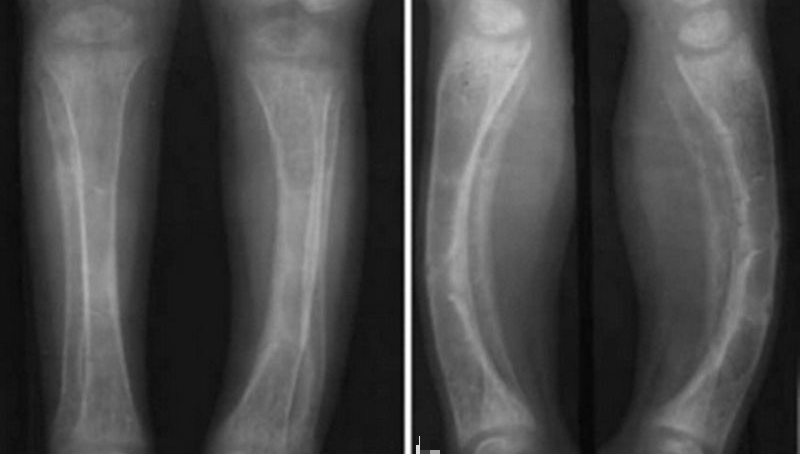

佝偻病和骨软化是维生素D缺乏在临床特有的表现,其他症状还有:关节松弛、脊柱弯曲、贫血、脱发、膝内翻、胸廓畸形等。

佝偻病发生于生长发育中的婴幼儿及儿童时期,骨软化症发生于成年人,临床表现存在明显的差别。